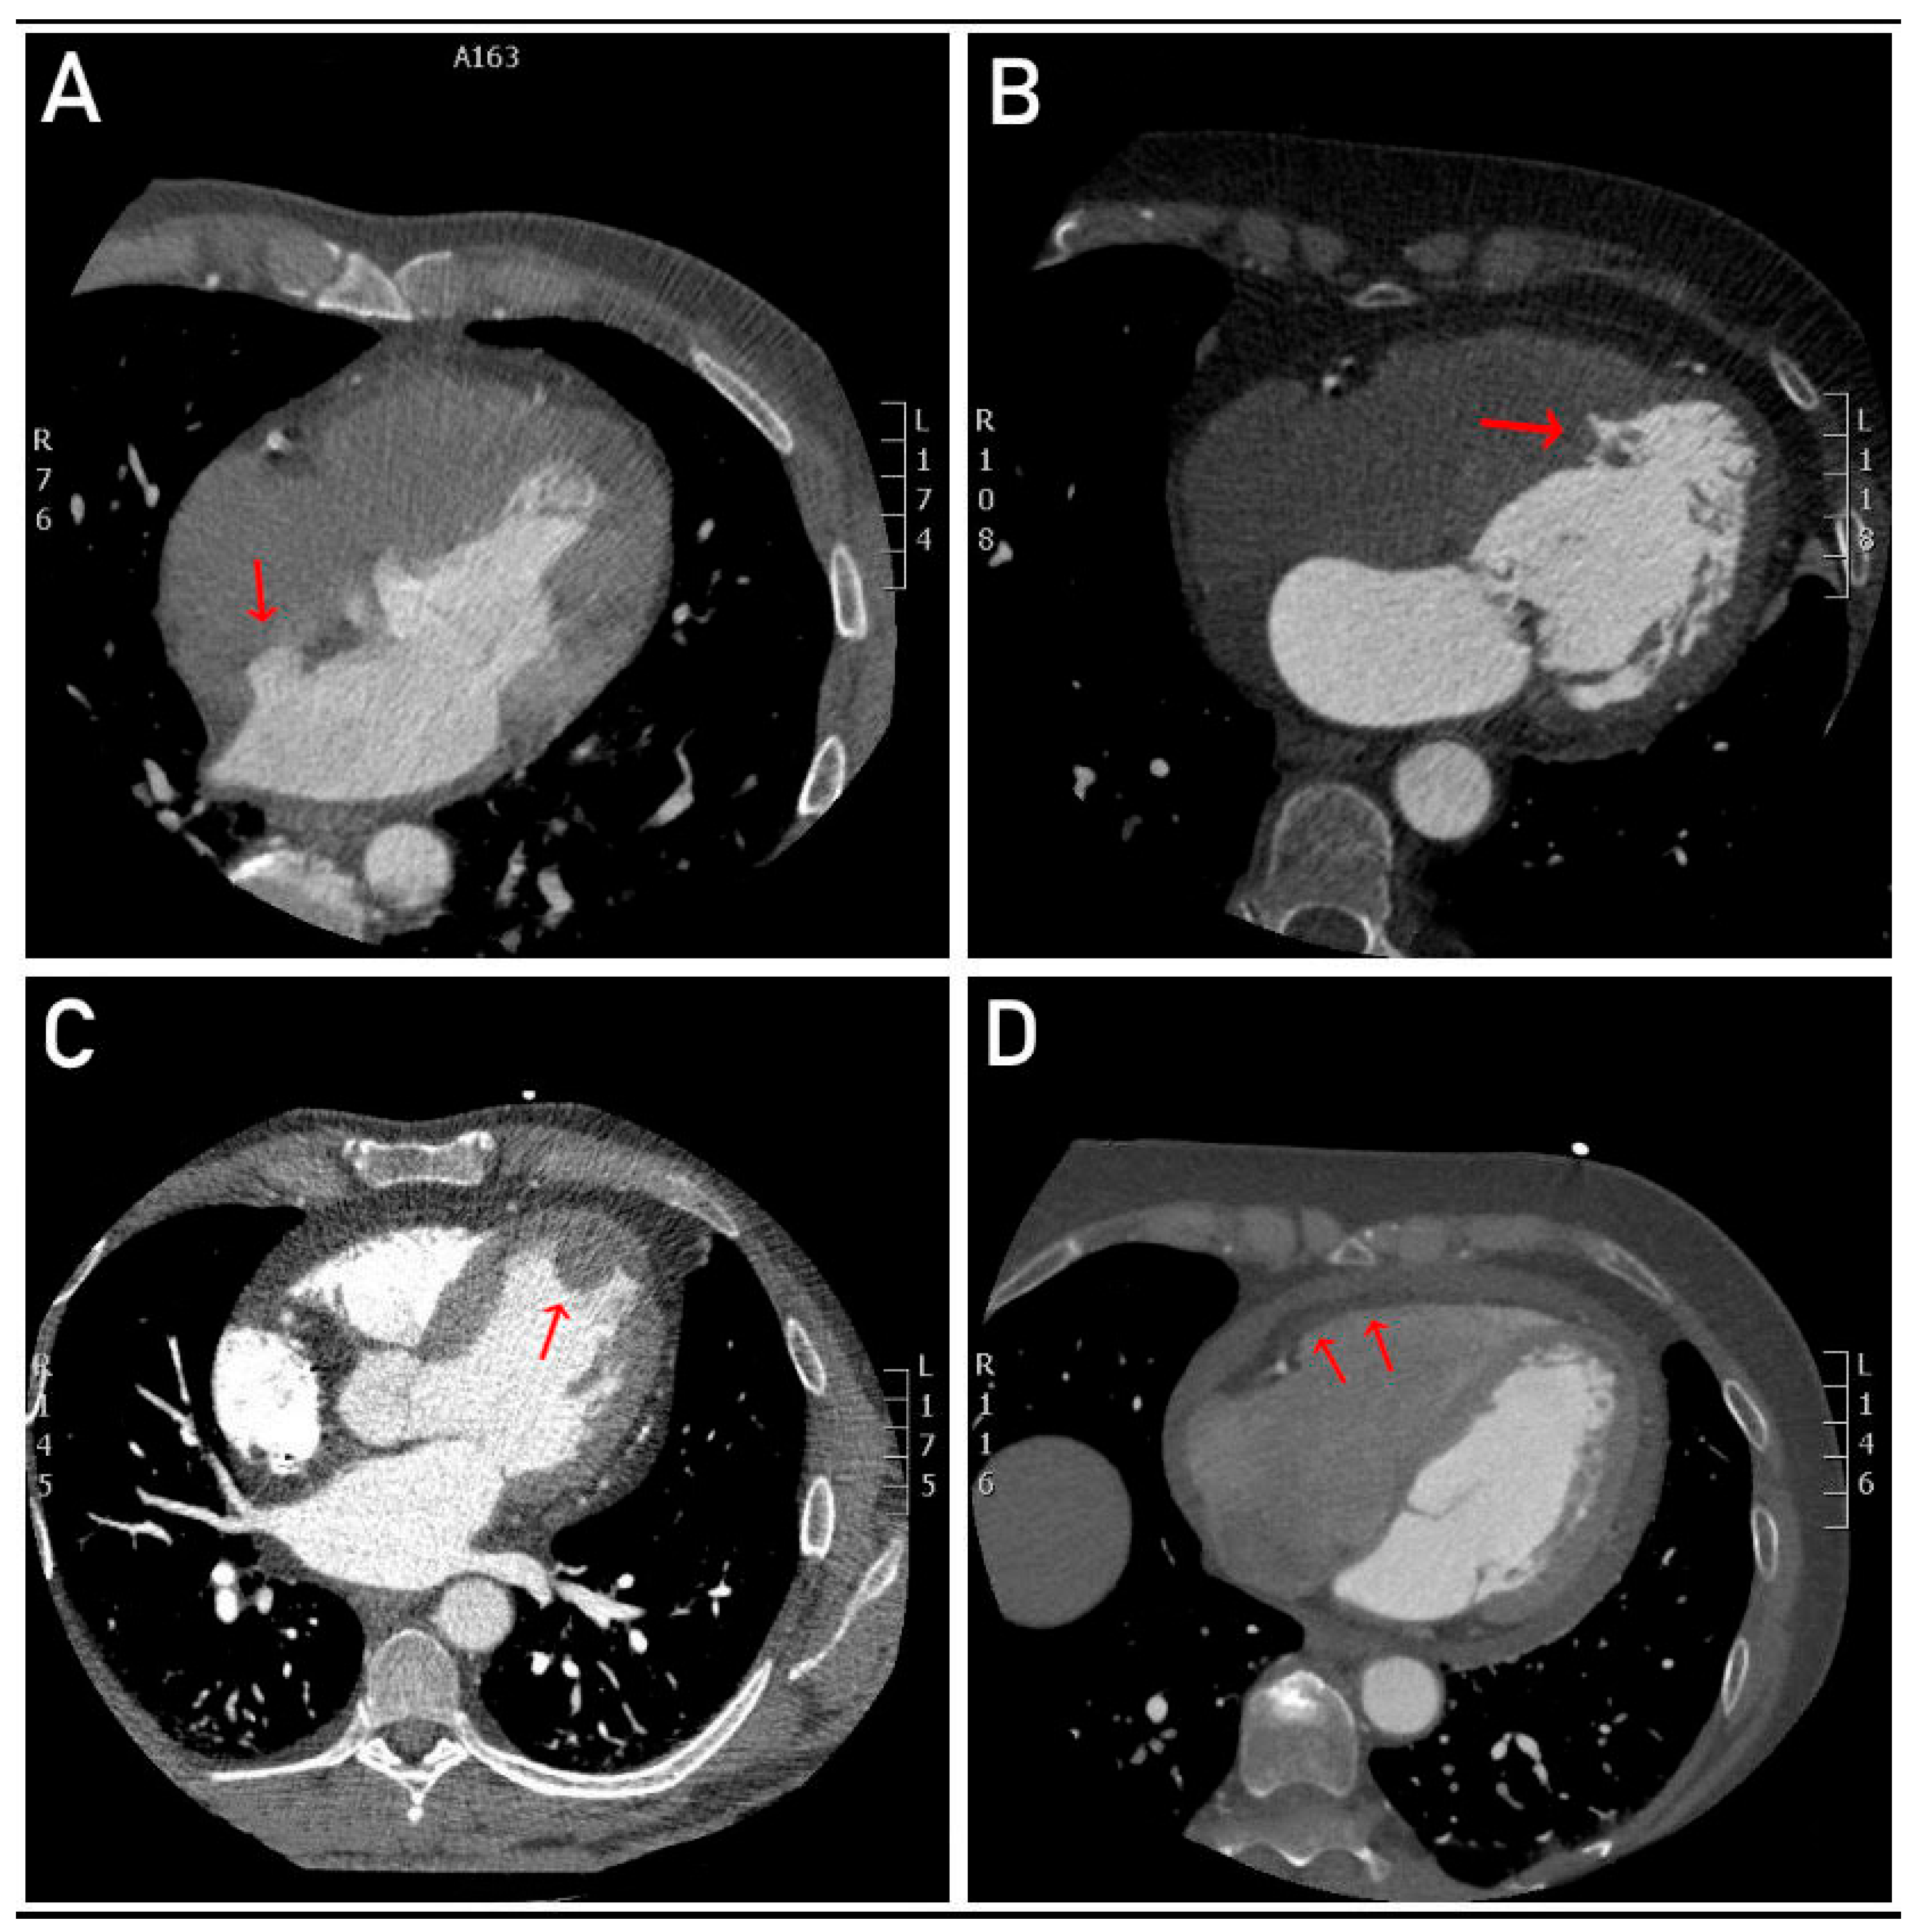

- Interatrial Septal Aneurysm: An abnormal bulging or pouching of the interatrial septum, which may be associated with an increased risk of embolic events, such as stroke (Figure 3).